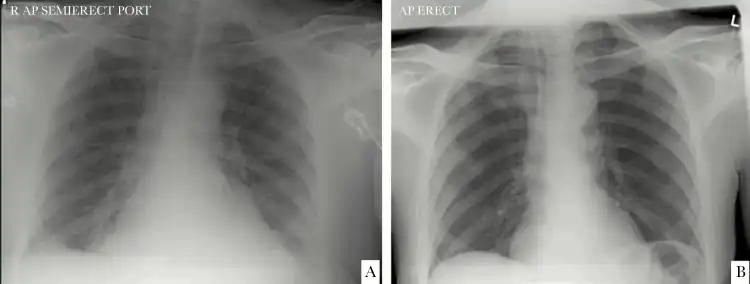

a)Chest x-ray from individual at time of CoV-HKU1 diagnosis b) chest x-ray 1-year before

HCoV-HKU1 was first detected in January 2004, in a 71-year-old man who was hospitalized due to acute respiratory distress syndrome and radiographically confirmed bilateral pneumonia. The man had recently returned to Hong Kong from Shenzhen, China.[2][9]